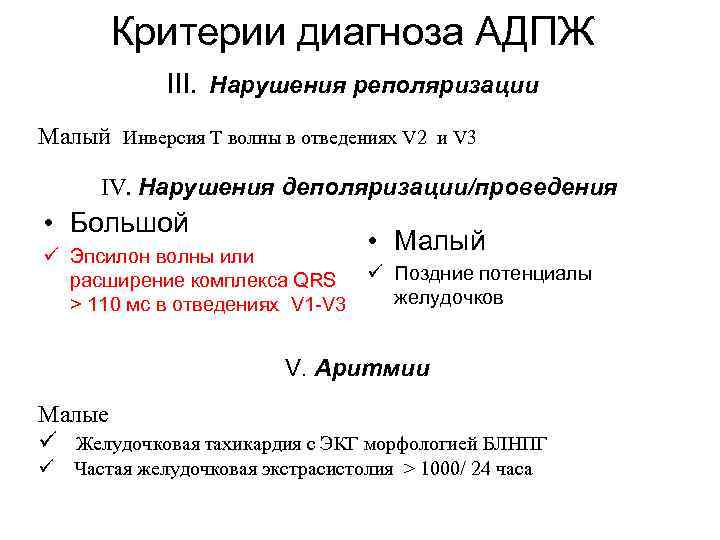

Критерии диагноза АДПЖ III. Нарушения реполяризации Малый Инверсия Т волны в отведениях V 2 и V 3 IV. Нарушения деполяризации/проведения • Большой ü Эпсилон волны или расширение комплекса QRS > 110 мс в отведениях V 1 -V 3 • Малый ü Поздние потенциалы желудочков V. Аритмии Малые ü Желудочковая тахикардия с ЭКГ морфологией БЛНПГ ü Частая желудочковая экстрасистолия > 1000/ 24 часа

Критерии диагноза АДПЖ III. Нарушения реполяризации Малый Инверсия Т волны в отведениях V 2 и V 3 IV. Нарушения деполяризации/проведения • Большой ü Эпсилон волны или расширение комплекса QRS > 110 мс в отведениях V 1 -V 3 • Малый ü Поздние потенциалы желудочков V. Аритмии Малые ü Желудочковая тахикардия с ЭКГ морфологией БЛНПГ ü Частая желудочковая экстрасистолия > 1000/ 24 часа